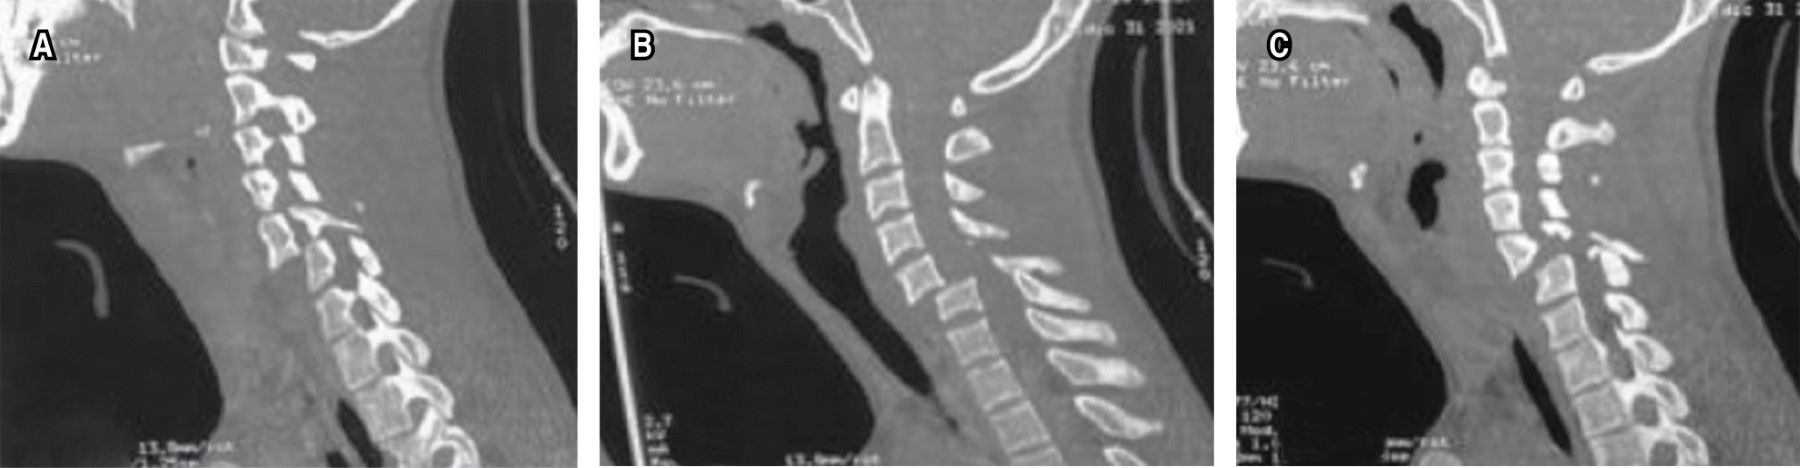

Introducción: la luxación cervical subaxial es una grave lesión, usualmente debido a un trauma de alta energía. El manejo es controvertido, más aún cuando el cuadro neurológico está intacto. Tener los estudios necesarios para evaluar el método de reducción (abierto o cerrado), así como la mejor opción de abordaje (anterior, posterior o 360°). Presentación de caso: paciente masculino de 19 años con historia de accidente de motocicleta, asistido en Hospital Regional de Petén, Guatemala. El examen neurológico evidencia función sensitiva y motora completa, radiológicamente (rayos X y tomografía) con fractura luxación C5-C6. Paciente fue inmovilizado y transferido a nuestro centro hospitalario. Al ingreso, se le realiza tracción esquelética con peso de 12 kg, con obtención de reducción parcial. Posteriormente, se realizó una instrumentación mediante abordaje posterior de C3-C7, el paciente evolucionó con adecuada función neurológica. Conclusión: el manejo de las luxaciones subaxiales sigue siendo controversial, especialmente en pacientes con un cuadro neurológico estable. La evaluación clínica adquiere un papel fundamental en centros hospitalarios sin acceso a resonancia magnética, ya que la reducción cerrada puede ser una opción efectiva siempre que se acompañe de una vigilancia neurológica continua. Asimismo, el abordaje posterior permite favorecer la cicatrización de los elementos posteriores y facilita la evaluación futura para un posible retiro del material, considerando la preservación de los discos intervertebrales.

Figura 1